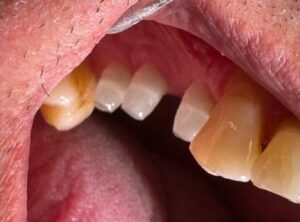

Impianto in zirconio vs impianto titanio impianto in titanio e corona-dente naturale-impianto zirconio e corona

Casi clinici risolti con impianti bianchi in ossido di zirconio whiteSKY/ Sistema Ceralog/ Patent